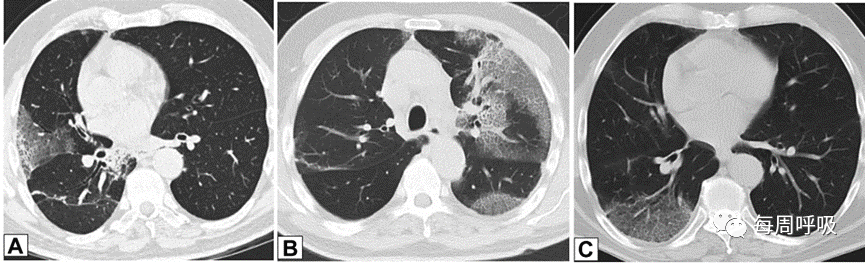

这种类型包括表现为线状不透明的实质条带,通常延伸到胸膜表面,通常先于磨玻璃样或实变(图15)。其他表现包括小叶周围增厚和具有反晕外观特征的病变(图16)。这个标志,也被称为“环礁征”,其特征是中央磨玻璃不透明(GGO)和外围实变。这些成像模式有着惊人相似的特征,通常可以在相同的情况下识别,甚至在同一张图像上。OP和慢性嗜酸性粒细胞性肺炎之间有相当多的共通之处,特别是当病变主要分布在上叶时。

图16 环礁征或反晕征。一名慢性持续性咳嗽和劳力性呼吸困难1年、体重减轻的32岁男性的CT扫描图像轴位(A)和冠状位(B)图像显示双侧中心磨玻璃样病灶完全被周围致密实变所包围,即反晕征或环礁征(A和B中红色箭头)。也存在不完全晕征(A和B中白色箭头)和小叶周围增厚(B中黄色箭头)。肺活检结果证实为机化性肺炎。